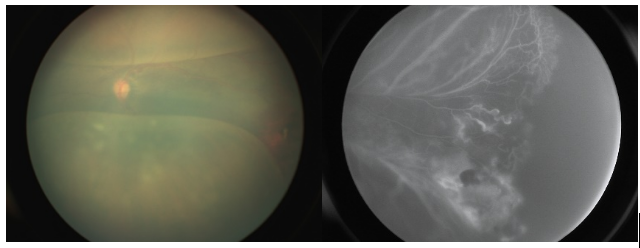

男婴,早产胎龄 29周+2天,出生体重1470g,38周+3天时外院做早产儿筛查诊断左眼ROP,眼内抗VEGF注药后4天复查视网膜出血好转 (外院);41周时检查发现左眼视网膜脱离,又观察1周视网膜脱离加重,遂转至浙江省人民医院首诊。眼底彩色照片和眼底血管造影检查发现,患儿的眼底血管发育情况较差,再次抗VEGF治疗后6天检查发现视网膜脱离加重。结合患儿特点为视网膜层间和视网膜下出血、脂质沉积、纤维渗出;周边血管显示动静脉吻合,异常扩张和渗漏,未发育完全,颞侧成团的异常扩张血管,且与对侧眼ROP程度(2区1期,plus-)不相称。考虑ROP 合并Coats,为患儿进行经巩膜抽液+激光+糖皮质激素注射(因渗出反应明显)。术后1个月复查视网膜血管扩张及脱离明显好转。

左眼术前情况(浙江省人民医院首诊时):视网膜层间和下出血、脂质沉着、纤维渗出;动静脉吻合、异常扩张和渗漏;未见PLUS,与对侧眼ROP程度不相称

图片

右眼来院首诊时情况:2区1期,plus-

左眼治疗后术后一月情况:视网膜下液基本吸收,可见缓释药丸